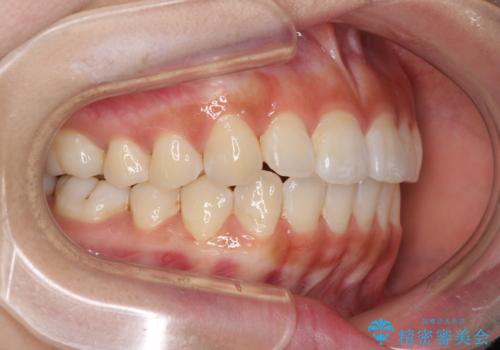

しっかりと装着時間を遵守してくださったので、思い通りの歯列に整えることができました。

結婚式前に終了させることができ、患者様には大変満足していただきました。